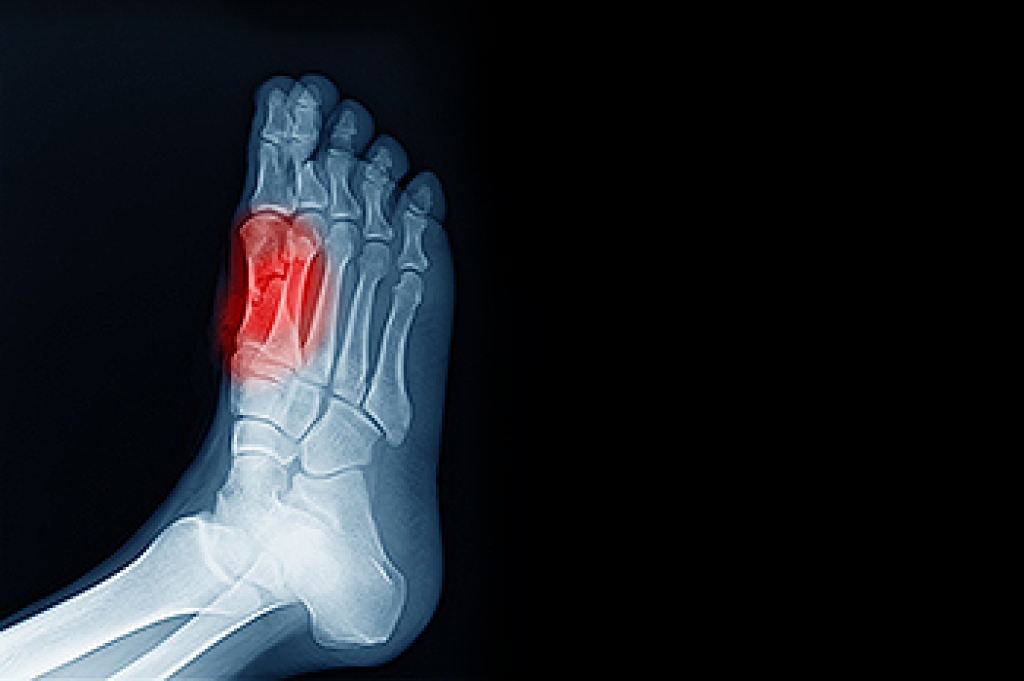

Foot and ankle injuries are a common occurrence when it comes to athletes of any sport. While many athletes dismiss the initial aches and pains, the truth is that ignoring potential foot and ankle injuries can lead to serious problems. As athletes continue to place pressure and strain the area further, a mild injury can turn into something as serious as a rupture and may lead to a permanent disability. There are many factors that contribute to sports related foot and ankle injuries, which include failure to warm up properly, not providing support or wearing bad footwear. Common injuries and conditions athletes face, including:

- Ankle Sprains

Sports related injuries are commonly treated using the RICE method. This includes rest, applying ice to the injured area, compression and elevating the ankle. More serious sprains and injuries may require surgery, which could include arthroscopic and reconstructive surgery. Rehabilitation and therapy may also be required in order to get any recovering athlete to become fully functional again. Any unusual aches and pains an athlete sustains must be evaluated by a licensed, reputable medical professional.